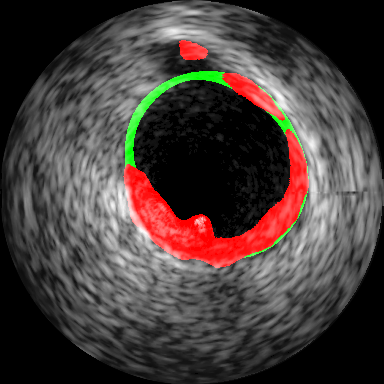

The architecture of the FCN used is illustrated in Fig. 2. It consists of an encoder unit, consisting of convolution and maxpooling layers and a decoder unit consisting of convolution and unpooling layers. The encoder resembles a VGG11 [5] barring the terminal classification layer. Feature maps are downsampled, and the number of features maps increases progressively with layer. The decoder is built to match activation map sizes in layers matched to depth in encoder with use of pooling index transferred for unpooling operation. This improves the boundary segmentation preserving conformity around small structures which is similar to the SegNet [4]. However, max pooling in encoder with a SegNet typically leads to the loss in subtle information related to smaller structures which progressively vanishes across successive depths. To address these limitations, we introduce the activation concatenation concept similar to that used in the UNet [6] which is of relevance to biomedical image segmentation tasks. We have employed ReLU [16] as an activation function in all layer except for the terminal layer of decoder where we have used sigmoid activation function [16] to force the output towards the [0,1] extremity. The network is trained with weighted binary cross-entropy (WCE) [16] loss function. Weights are calculated using a morphological distance transform giving higher weights to the pixels closer to the contour as illustrated for the IVUS in Fig. 3(c) and Fig. 3(j) for thyroid. The idea of using both maxpool indices and concatenating techniques helps in improving the preciseness of localization. The input is a grayscale image, and the first layer of the encoder provides an output with channel feature map to match input size expected in a VGG11.

Intravascular Ultrasound Segmentation: We have used IVUS data from the 2011 MICCAI workshop [8] which is composed of pullbacks of different patients acquired at MHz (Dataset B). The proposed method is compared with nine different methods, where eight approaches have been reported earlier in [10]. In Table 1, we have included only the best results among the participants (P1-P8) in [8]. Subsequently 2D visualization of segmented IVUS contours are presented in Fig. 3(d) - (g) and the lumen and external elastic luminae border segmentation in the whole pullback is visualized111Supplementary material. The proposed method outperforms the recent related prior art [11] as presented in Table 1.